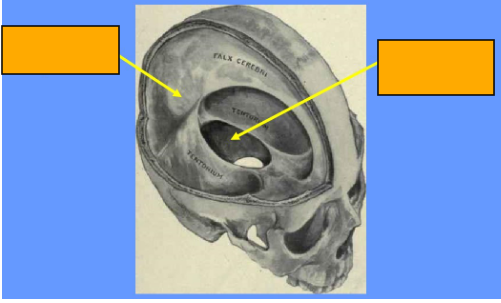

What divides the supratentorial compartment

divided by the falx cerebri into the left and right supratentorial space which can communicate with each other and with the infratentorial space

What is the falx cerebri

vertical fold of the dura mater located in the longitudinal fissure that separates the left and right cerebral hemispheres

Anterior, superior and posterior attachements of the falx cerebri

anterior- crista galli

posterior- internal occipital protuberance

superior- internal surface of calvaria along the sagittal suture

Label this image